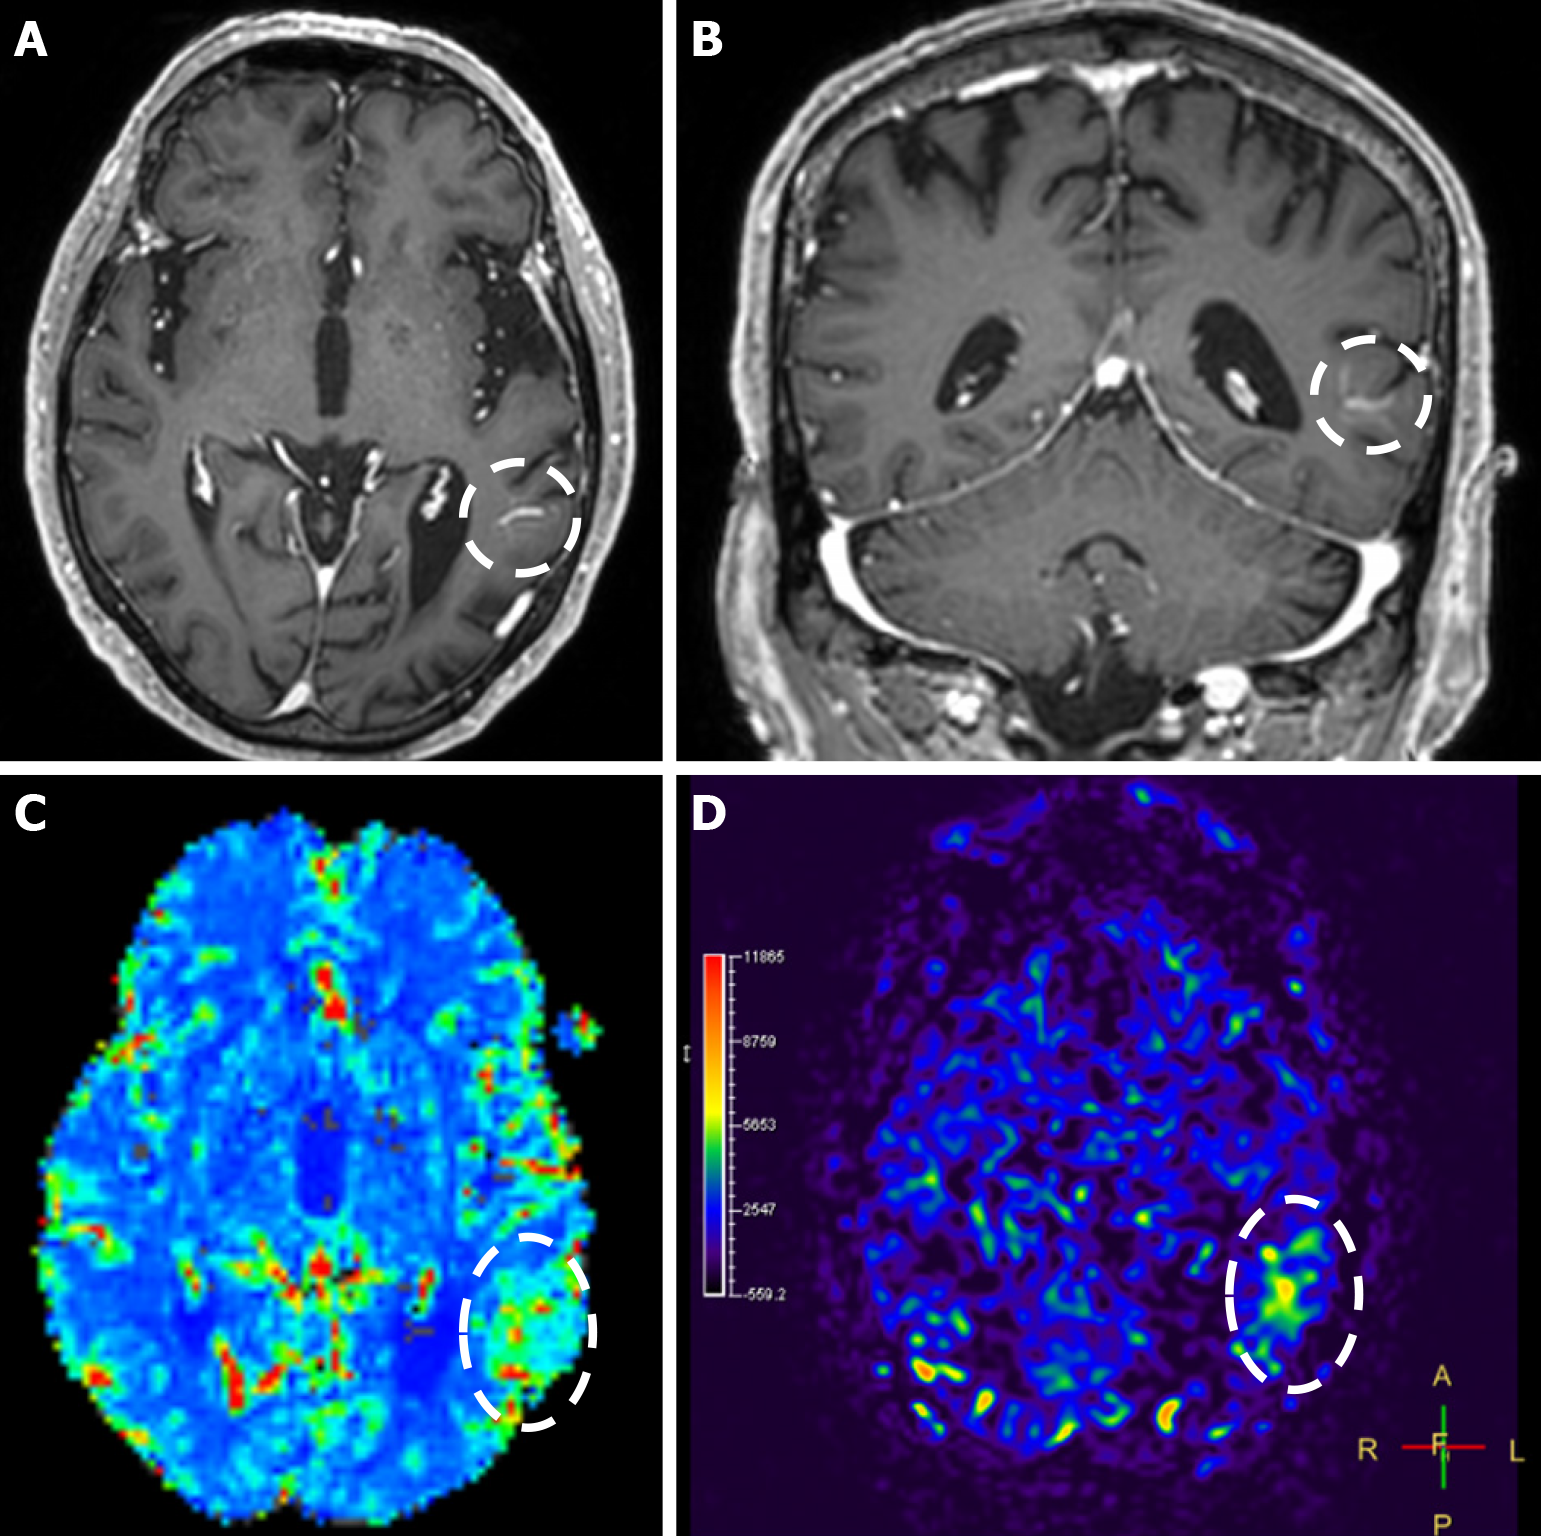

Imaging findings in coexistent DVAs and CMs will be the combination of those described for each malformation separately. Awareness of the possibility of their coexistence may prove invaluable in clinical practice. This is because recognition of a DVA close to a brain hemorrhage may raise suspicion for an underlying CM as the most likely etiology. Additional examinations and follow-up imaging following hematoma resolution will further enhance diagnostic confidence. Figures 8, 9, 10 and 11 illustrate clinical examples in which identifying the synchronous presence of a DVA adjacent to a brain hemorrhage (or suspected brain hemorrhage) enabled the diagnosis of a probable underlying CM as the most likely etiology, thereby avoiding unnecessary examinations or interventions.

The clinical applicability of the Zabramski classification is still being investigated. A retrospective cohort study evaluating the imaging evolution and clinical trajectory of 255 untreated patients with sporadic CMs over a follow-up period of approximately five years provided evidence that the Zabramski classification may facilitate risk stratification and contribute to treatment planning, particularly in determining the necessity for surgical intervention[89]. Furthermore, a recent study by Saari et al[88] established an association between the radiological characteristics of the Zabramski classification and their clinical relevance, emphasizing that type I lesions have a higher likelihood of becoming symptomatic. Nikoubashman et al[90] suggested an additional category (type V lesions) accounting for cavernomas presenting with gross extralesional hemorrhage. Various examples of CMs on CTs and MRIs, including familial cerebral CM cases, are shown in Figures 4, 5 and 6.